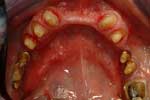

Caso 16

Riabilitazione superiore su impianti con protesi parzialmente rimovibili ed inferiore su impianti fissa

Il sorriso del paziente